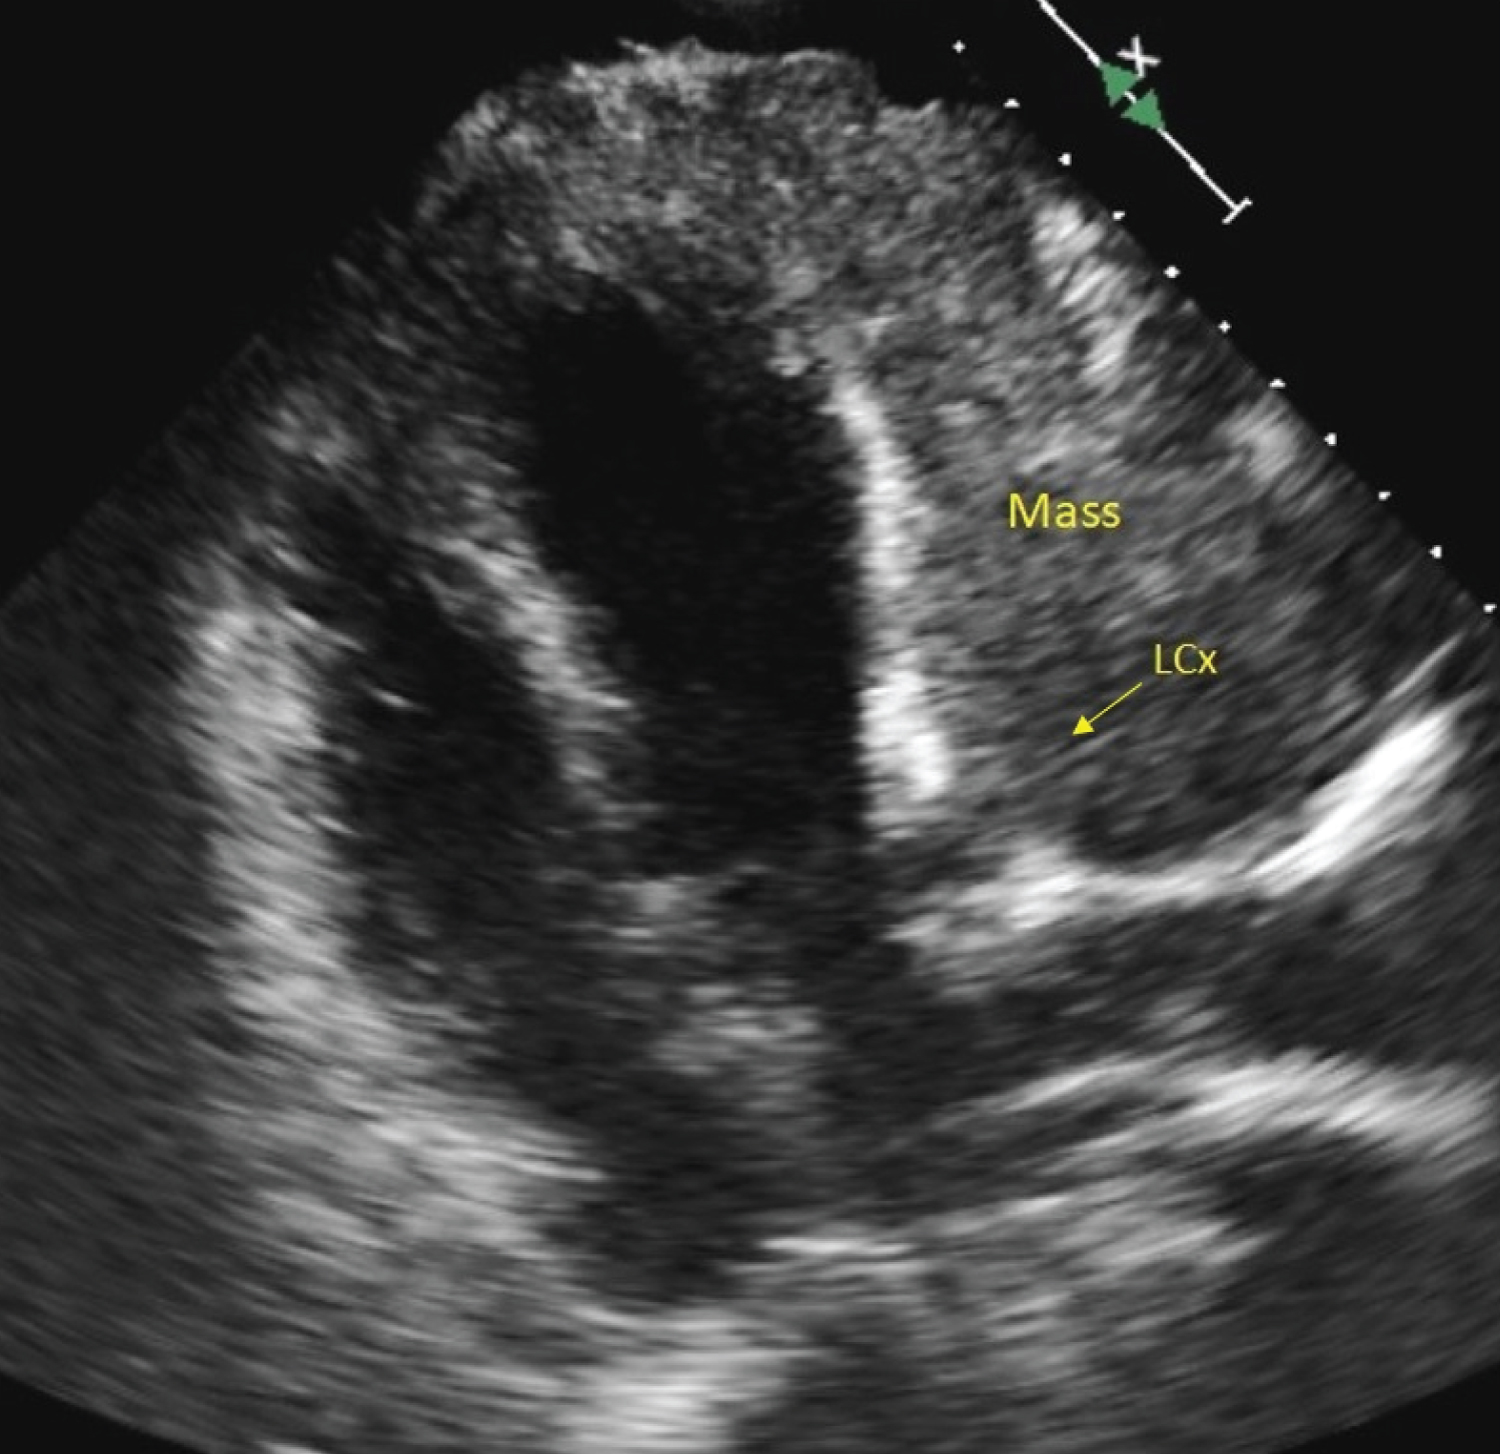

This case is about a 65-year-old man who was diagnosed of stage IV Thymic Carcinoma in 2012, with two recurrences in 2013 and 2015. He underwent a surgical treatment in 2012 with surgical excision of the mediastinal mass, right upper and medium lung lobe, and upper left lobe, pericardiectomy, excision of phrenic nerve, IVC, innominate left vein and portion of innominate right vein, followed by different radiation and chemotherapy. From 2018, the patient was CPAP addicted for respiratory failure. At the time of our meeting with the patient, an experimental protocol with Pembrolizumab was still in progress. He was admitted to emergency department in a cachectic status with worsening dyspnoea in the last few days. The Glasgow Coma Scale was 15/15; the blood pressure was 90/60 mmHg and the pulse rate 74 bpm. The auscultation was totally subverted with harsh lung sound, heart tones were difficult to hear. The biochemistry panel revealed TnT hs 35 ng/L, CRP 80 mg/L, creatinine 80 umol/L, GFR 90 ml/min/1.73 m2. He denied any chest pain, and he complained of dyspnoea and weakness. The ECG showed an ST-elevation in DI-aVL and V4-V6 suggesting an ACS (Figure 1), so the patient has been urgently transferred to hemodynamic units. An emergency coronary angiogram was performed, but the exam showed no significant coronary artery stenosis (Figure 2). The transthoracic echocardiography performed in the cath lab revealed a mass infiltrating the left ventricular myocardium with consequent akinesia of lateral and anterior wall without impairment of the right ventricle or valvular disease (Figure 3). For a better diagnostic picture, we performed a thoracic CT scan (Figure 4). The exam revealed a mass of 17*10*12 cm without a cleavage plan from the LV, which infiltrated the myocardium surrounding the left circumflex coronary artery. This finding was interpreted as the cause of the ST-elevation.

Figure 3: Transthoracic Echocardiography: Mass infiltrating the left ventricular myocardium. View Figure 3